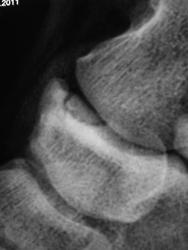

Да, перелом основания пятой плюсневой кости есть. Линия перелома поперечная, а та, что продольная - это зона роста. А что за фрагмент у верхушки наружной лодыжки? Вероятнее всего старый перелом лодыжки, потому что дополнительных точек окостенения наружная лодыжка не имеет.

А, как Вам ладьевидная кость?

Смущает и участок помеченный стрелками.

Стрелки же не на ладьевидную кость указывают?

Добавочный эпифиз 5 плюсневой кости с эпифизеолизом и переломом основания. В ладьевидной кости добавочная кость tibiale externum. Возле кубовидной кости, вероятнее всего, os cuboideum secundarium

Прикольно, болезнь Кёнига в ладьевидной кости... Открытие?

По всей видимости - случайная находка...